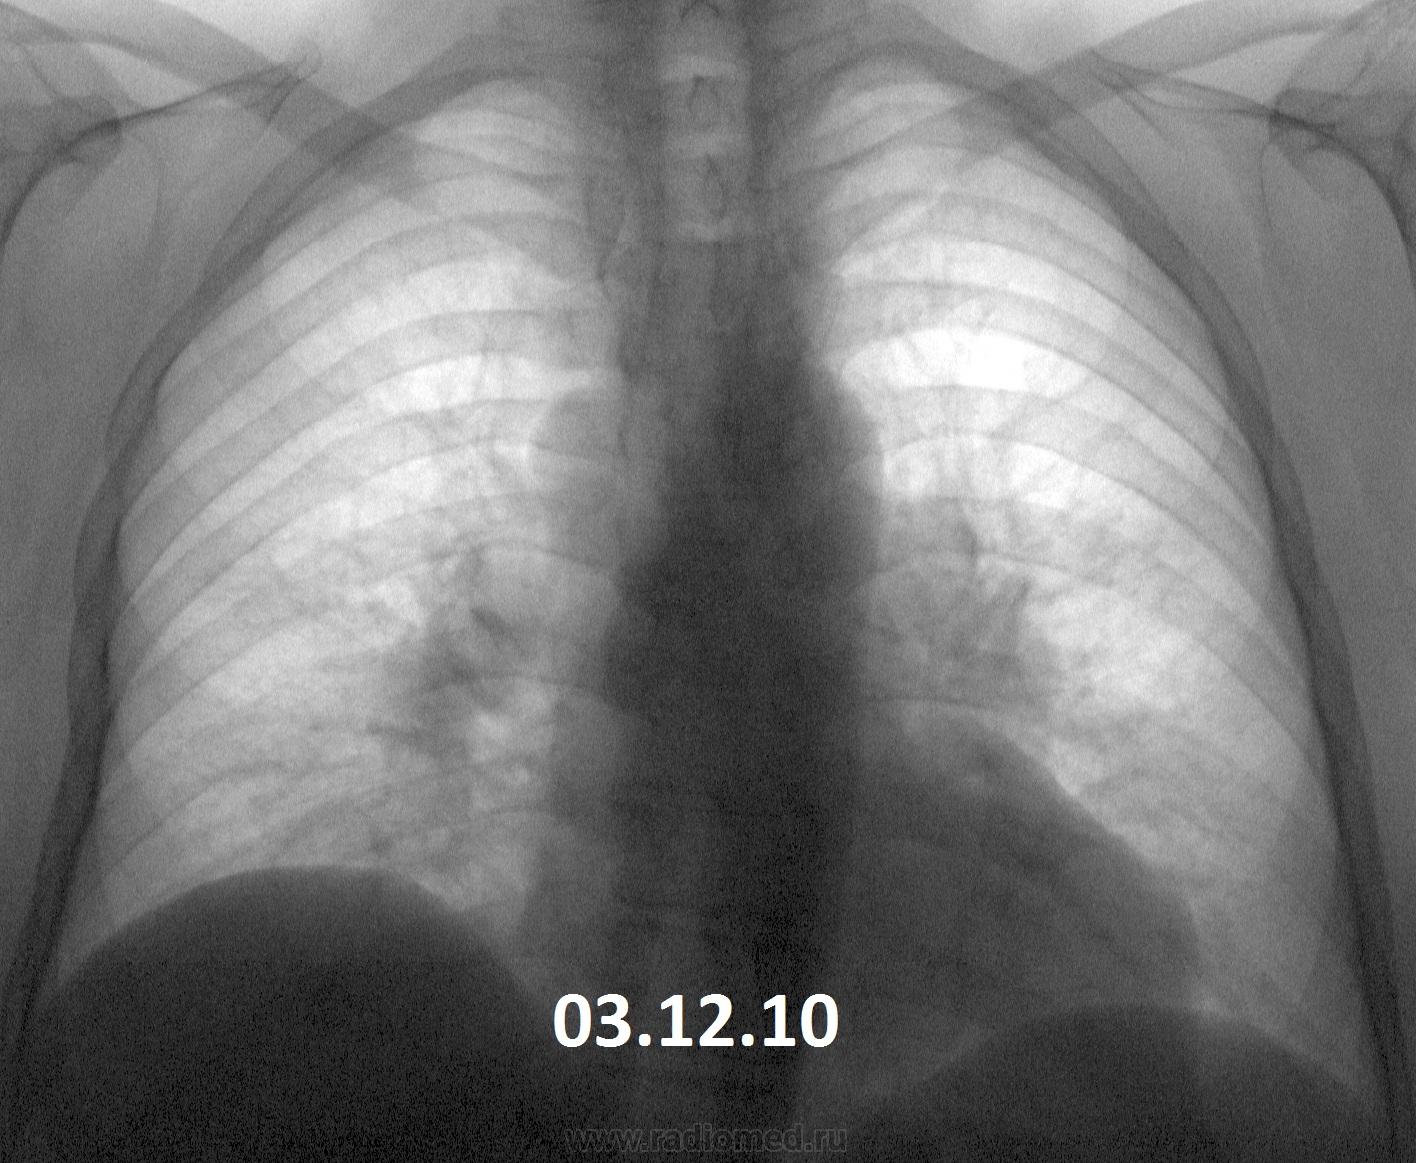

Вот такая динамика. В 2010 г. - в один день вдох-выдох- такая методика у предыдущего флюородоктора. Жалоб нет (кроме сердечных). Согласно КТ ОГК от декабря 2013 - лимфоаденопатия (как говорится - ни вашим, ни нашим). Вроде уже обращено внимание, пациент(ка) это ощутил. Успокоиться?

Мне кажется, такая динамика за 3 года не впечатляет.

Картина одинаковая. Увеличение л/узлов средостения и лёгких. Хоть с каким диагнозом наблюдается. Сердечные проблемы здесь ни при чём, они только в ЗАГСе.

Динамики вроде нет.Похоже на саркоидоз.

Нет. Без томографии не обойтись. Если подтверждается лимфаденопатия, следующий этап - морфологическая верификация. А как по другому? Конечно, надо учитывать местные возможности.

Есть конечно, тот лимфоузел побольше стал. Диагноз однозначно нужно верифицировать.

По мне так это 1-2-3 sign при саркоидозе.